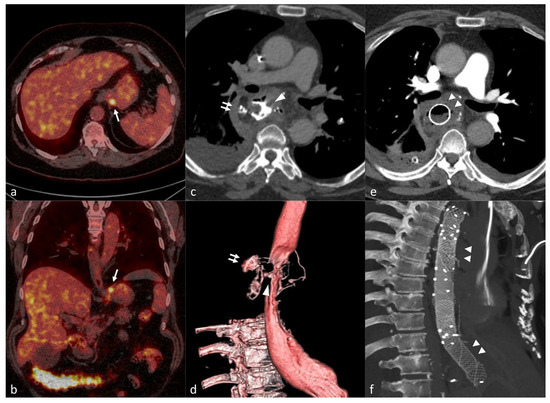

Figure 1. Preoperative axial (a) and oblique coronal (b) fused images of 18F-FDG PET/CT * showing focal FDG uptake in the gastric cardia (single arrow) in a 63-year-old female patient with gastric cardia adenocarcinoma. The patient underwent minimally invasive esophagectomy with gastric tube reconstruction (Ivor Lewis) after neoadjuvant chemotherapy. Axial (c) and 3D reconstruction (d) images of postoperative CT scan with oral contrast on the 6th postoperative revealing leakage (double arrows) due to a large defect in the gastric conduit wall (arrowhead). Three overlapping stents were endoscopically placed to cover the defect as seen on the axial (e) and oblique sagittal MIP (f) of the follow-up CT scan (double arrowheads). * 18F-FDG PET/CT: 18F-Flurodeoxyflucose Positron Emission Tomography/Computed Tomography. MIP: Maximum Intensity Projection.

Anastomotic leakage (AL) is one of the most dreaded complications following esophagectomy Figure 1. While the overall 30-day mortality in patients undergoing esophagectomy is 2–3%, it can increase to 17–35% in patients with a sustained leakage [13]. In addition to increased mortality, AL is related to significant postoperative morbidity, prolonged hospital stays, increased recurrence rates, and a worse long-term quality of life [14,15]. The overall incidence of AL after esophagectomy ranges between 10 and 20%, with an associated mortality of 5–10%, indicating a wide variety in the surgical practices used in esophageal cancer and the management of AL worldwide [16]. A consensus with regard to the definition of an AL is still under discussion, and it is a continuous challenge for the scientific community to understand, prevent, diagnose, and treat AL which is a critical, costly, and potentially lethal postoperative complication [17].